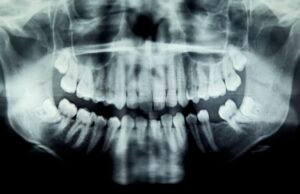

Condição de diagnóstico: o problema dental da menina causou olhos que...

Paciente: Uma garota de 6 anos da CisjordâniaSintomas: A menina foi trazida para seu dentista primário porque estava com dor de dente perto de...